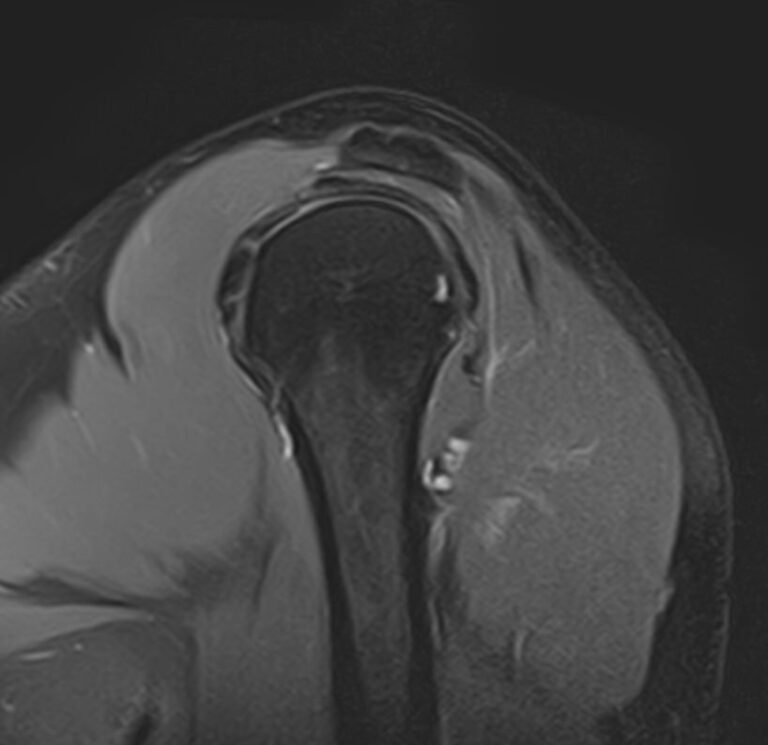

Для того, чтобы оценить состояние шейных позвонков с прилегающими тканями и одновременно визуализировать плечевой сустав, в нашей клинике выполняется комплексное обследование, включающее два протокола: МРТ шейного отдела позвоночника и МРТ плечевого сустава.

Метод МРТ позволяет оценить состояние всех анатомических областей шейного отдела позвоночника: костную структуру позвонков, спинной мозг с отходящими от него нервными корешками и окружающие мягкие ткани. Протокол обследования плечевого сустава включает оценку костной структуры, суставной капсулы, полости сустава с выстилающей его синовиальной оболочкой, связок, сухожилий, мышц и окружающих мягких тканей.